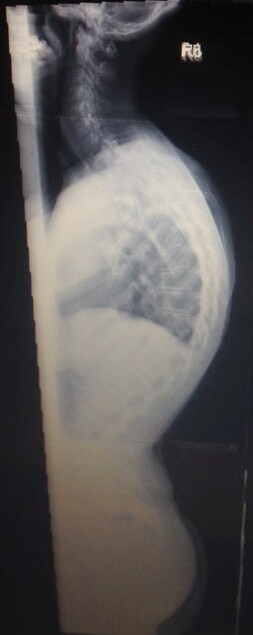

Diagnose: thorakale Kyphose 80 Grad

Meine Name ist Claudia bin 30 Jahre und habe eine Hyperkyphose von 80 Grad die im November 2013 endlich festgestellt wurde, eine leichte Skoliose hatte ich schon von Kind an . Am Ende war es so das ich seit über 20 Jahren mit Schmerzen lebe , bis mir vor 4 Jahren wegen unerträglichen Schmerzen eine Bandscheiben OP gemacht wurde da es angeblich davon kam!!! ( nur leider lagen diese ganzen Ärzte bei ( ca.20 Ärzte von Orthopäden, Neurologen und so weiter ) denen ich im lauf der 20 jahre war alle falsch , alle meinten das wären die Bandscheiben :(

Seit November 2013 bin ich im BGU Frankfurt am Main daher auch die Diagnose wegen einer 2. Meinung war ich auch noch in Würzburg, diese kamen auf das gleiche . Irgendwie froh bin ich schon das ich nun endlich weiss was ich habe und wie es zu behandeln ist .

Im Anhang 2 Bilder von mir

IMG-20131213-WA0003~2.jpg

IMG-20131213-WA0003~2.jpg (22.58 KiB) 6612 mal betrachtet